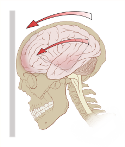

(Wikipedia illustration:

Acceleration

(g-forces) can exert rotational forces in the brain, especially the

midbrain

and

diencephalon

)